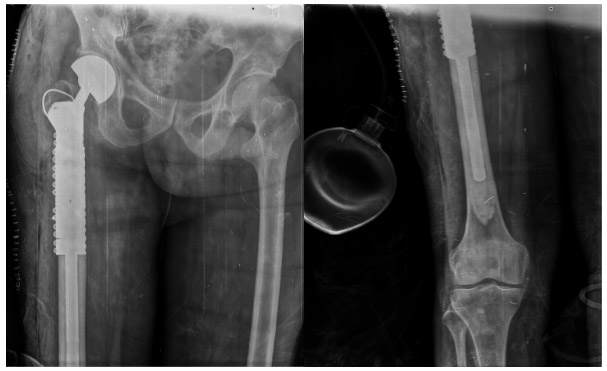

Post-Surgery: The X-ray shows the tumor prosthesis that was implanted after the upper part of the femur was removed.